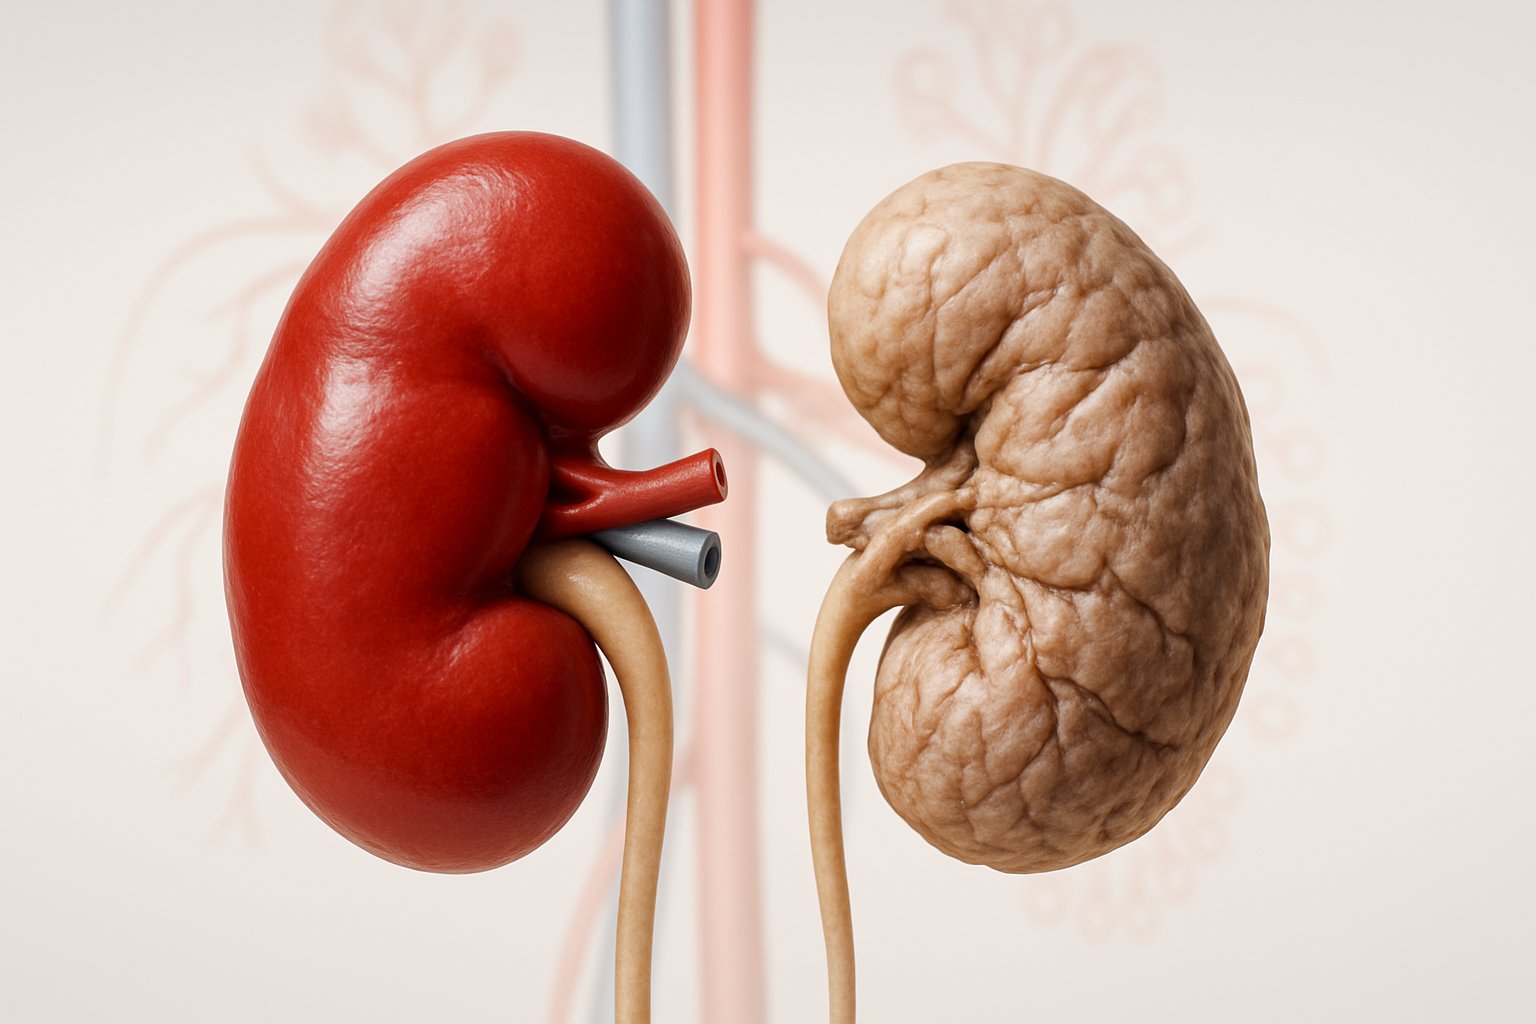

Definition of Kidney Failure

Kidney failure is a condition in which one or both kidneys no longer work on their own[1]. Medical professionals also call this condition renal failure or end-stage renal disease.

Loss of Kidney Function

Kidney failure means 85-90% of normal kidney function is gone[4]. The remaining kidney tissue cannot handle the body’s needs.

Chronic kidney failure develops slowly over months or years. This gradual decline often goes unnoticed in early stages.

Chronic kidney failure is permanent. Treatment focuses on slowing progression and managing complications rather than curing the condition.

End-stage renal disease occurs when 85-90% of kidney function disappears[4]. This represents the final stage of chronic kidney disease progression.

The transition happens gradually over months or years. Kidneys lose their ability to filter waste and excess fluid from blood. Toxins build up in the body causing serious health problems.